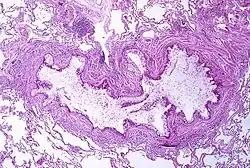

A tissue cross section of the airway showing a stained pink wall and an inside full of white mucous

Obstruction of the lumen of a bronchiole by mucoid exudate, goblet cell metaplasia, and epithelial basement membrane thickening in a person with asthma

Asthma is the result of chronic inflammation of the conducting zone of the airways (most especially the bronchi and bronchioles), which subsequently results in increased contractability of the surrounding smooth muscles.[21] This among other factors leads to bouts of narrowing of the airway and the classic symptoms of wheezing. The narrowing is typically reversible with or without treatment. Occasionally, the airways themselves change.[21] Typical changes in the airways include an increase in eosinophils and thickening of the lamina reticularis.[20] Chronically, the airways' smooth muscle may increase in size along with an increase in the number of mucous glands.[20] Other cell types involved include T lymphocytes, macrophages, and neutrophils. There may also be involvement of other components of the immune system, including cytokines, chemokines, histamine, and leukotrienes among others.[20]